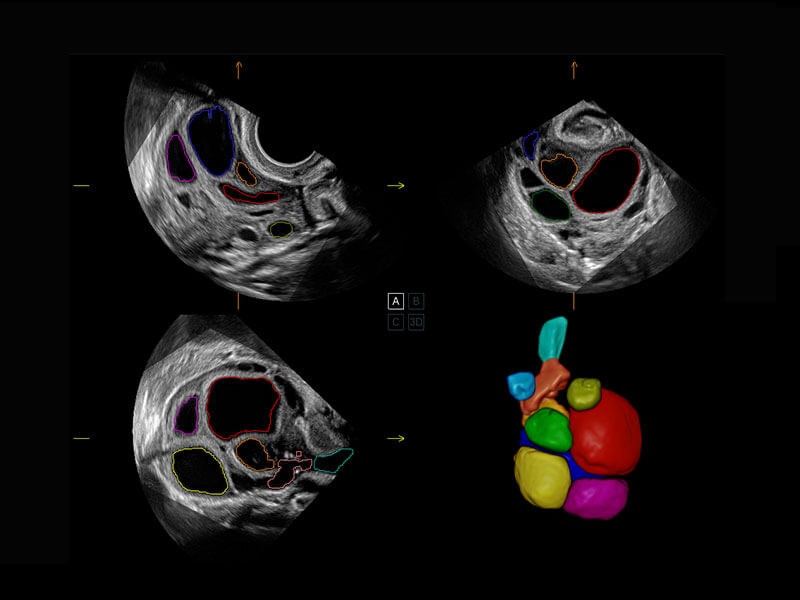

P60提供简单易学易用的高端诊断工具,为您中晚孕筛查提供快速清晰的解剖信息。

S-Fetus能够助您在实时扫查过程中自动识别标准切面、自动测量并录入报告。一个按键,即可快速、高效地获取胎儿生理指标,简化您的产科检查操作。